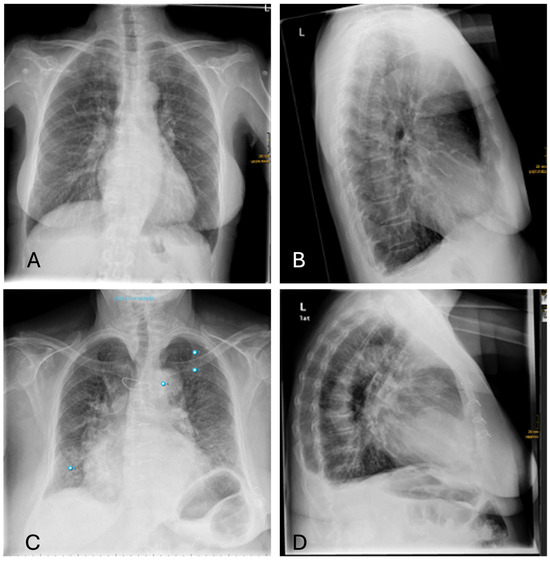

3.4.3. Nodules

Besides fractures, the detection of lung nodules also shows high discrepancies between software and human raters. Smaller nodules are sometimes overlooked by radiologists (Figure 7B), whereas pseudo-lesions—structures such as nipple shadows, catheter material or port needles as well as external foreign bodies—are sometimes falsely interpreted as pulmonary nodules by the AI (Figure 7D). These pitfalls occur only seldom with radiologists, who can easily correctly identify these items for what they really are. Similarly, transversely sectioned vessels or bronchi are diagnosed as round opacities indicative of pulmonary nodules due to their morphology. For pleura-adjacent nodules, the distinction from pleural plaques is not always clear.

False-negative findings occur, for example, due to the misinterpretation of a pulmonary nodule as pneumonia because of overlapping morphology. Additionally, the diagnosis of masses in the lingula segment of the lung is complicated by the overlap with the heart.

Figure 7. Inconsistencies of nodule diagnoses: (A)—false-positive AI interpretation of pulmonary mass in the lower lobe on the left as infiltration caused by pneumonia. (Note: Also false classification of Portcatheter as pneumothorax, again “aortic abnormality” and “rip fracture”); (B)—correctly identified nodule by AI overlooked by radiologist (Note: other finding incorrectly labelling “aortic abnormality”); (C)—False-positive nodule described by AI, really corresponding to the overlay of two ribs; (D)—False-positive nodule described by AI, really corresponding to external oxygen hose (Note: other findings incorrectly labelling “aortic abnormality” and “rib fracture”).